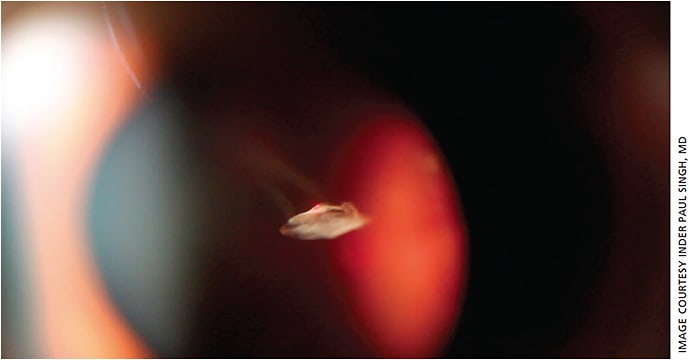

Visualization is key to providing spatial context during LFT. Without the proper technology, it is very difficult to identify many of the symptomatic floaters and confirm a safe distance from the posterior capsule and the retina. Surgeons need to be able to determine where they are within the vitreous in relation to other ocular structures, such as retina and lens. Limited visualization is a reason why some of the earlier studies demonstrated variable efficacy and safety; often they were only treating floaters right behind the lens (Figure 1).

With Ellex’s YAG laser illumination system (True Coaxial Illumination, or TCI), surgeons have full visualization of the entire vitreous from the lens to the retina. This is achieved by using a retractable, reflecting mirror designed to move out of the laser pathway during the treatment. The laser, the oculars and the illumination tower use the same optical pathway, allowing for coaxial illumination and thus simultaneous visualization of both the retina and the floater. This is important to prevent inadvertently disrupting the retina (Figure 2).